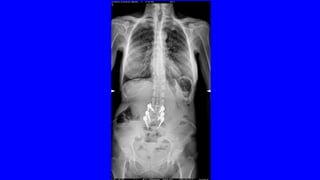

• ENCUESTA DE SALUD DEL INE: LA PREVALENCIA DEL DOLOR LUMBAR Y/O

CERVICAL EN ESPAÑA ES DEL 25% (> 10 MILLONES)

• PRIMER MOTIVODE CONSULTA MÉDICA • < 45 AÑOS ES EL PRIMER PROBLEMA INCAPACITANTE • EN EEUU ES EL MAYOR GASTO EN SALUD (IT, ANALÍTICAS, RX,RNM) • IMPLICA SUFRIMIENTO, DIFICULTAD PARA EL DESCANSO, TRISTEZA Y AL FINAL DEPRESIÓN: COMPONENTE PSICOSOCIAL • ENCUESTA DE SALUD DEL INE: LA PREVALENCIA DEL DOLOR LUMBAR Y/O CERVICAL EN ESPAÑA ES DEL 25% (> 10 MILLONES)